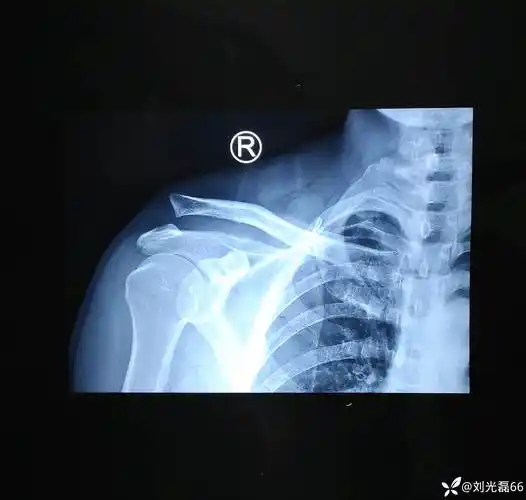

肩锁关节脱位

肩锁关节脱位4年

陈旧性肩锁关节脱位